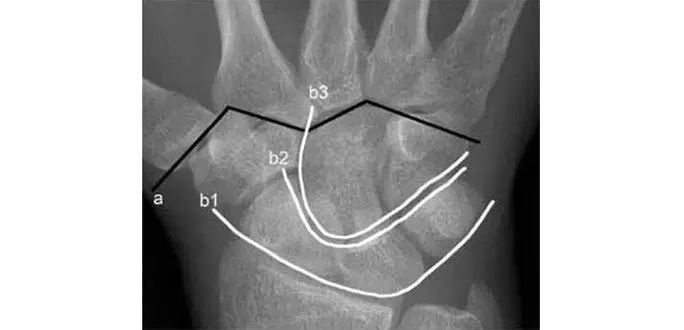

两条弧线如果不连通多半有脱位

若显示腕骨弧线不连续或各弧线不平行,或腕掌线M 形结构消失,应高度怀疑腕关节不稳或脱位。

Analyze - 腕骨弧线正位弧线不连续,侧位明显脱位。